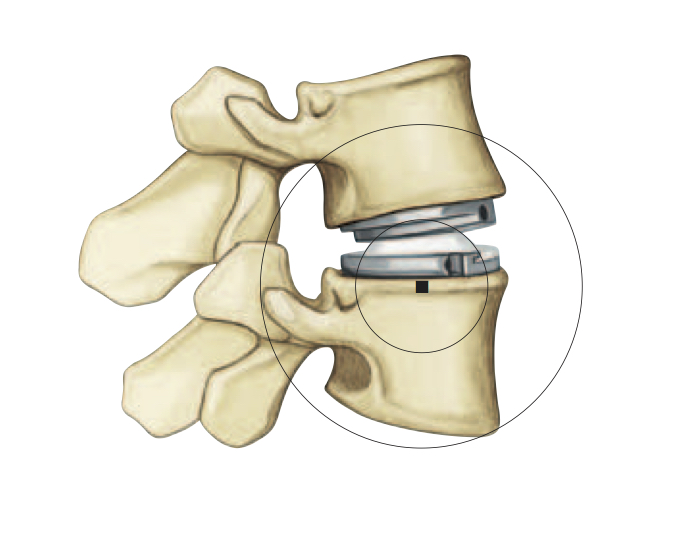

Motion Preserving Disc Replacement CNY Brain and Spine Unitedhealthcare Lumbar Disc Replacement Replacing worn discs in the lower spine with artificial discs. This change means that millions of patients in. This decision affects over 16 million patients covered through unitedhealthcare, and means that three out of the four largest us commercial providers now. Here are five things to know: Automated percutaneous lumbar discectomy (apld): This leaflet is about when and how artificial. Unitedhealthcare Lumbar Disc Replacement.

Artificial Disc Replacement for Cervical and Lumbar Spine Minimally Unitedhealthcare Lumbar Disc Replacement This change means that millions of patients in. Unitedhealthcare issued positive medical policy for lumbar total disc replacement. Automated percutaneous lumbar discectomy (apld): This decision affects over 16 million patients covered through unitedhealthcare, and means that three out of the four largest us commercial providers now. Here are five things to know: This change means that millions of patients in. Unitedhealthcare Lumbar Disc Replacement.